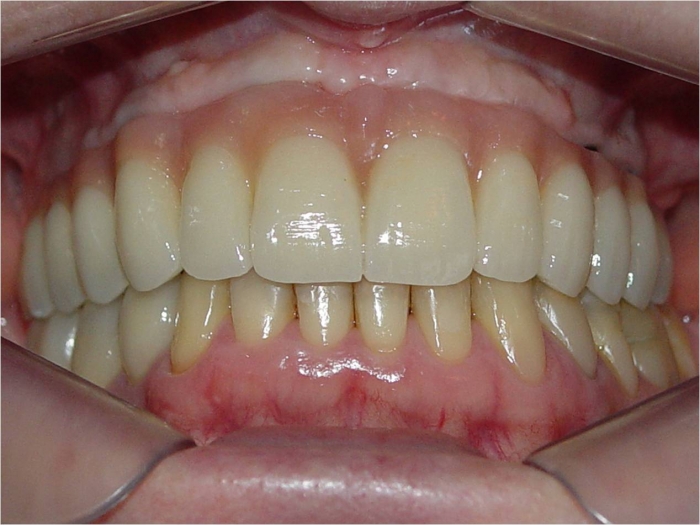

Prótese fixa superior em porcelana

Sorriso final, do caso terminado em fevereiro de 2014